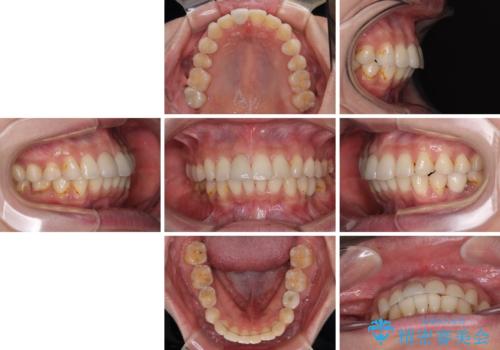

デコボコと乳歯の欠損 ワイヤー矯正とインプラント補綴治療

- 全体的なデコボコと左下乳歯部の欠損を気にして来院された患者様です。

乳歯が抜け落ちた後の後続永久歯が欠損しているため、スペースが残っておりました。

口元の突出感を気にしているのであれば欠損スペースを利用して抜歯矯正を行うことも可能ですが、横顔の印象はスッキリとしている状態であったため、矯正治療でスペースを閉じきることは不可能と判断し、インプラントによる補綴治療を行うこととしました。

第二小臼歯の欠損によるが乳歯残存や欠損が多く、この乳歯は後続永久歯に比べて幅が非常に大きいため、教聖地料によるスペースクローズが難しいことが一般的です。